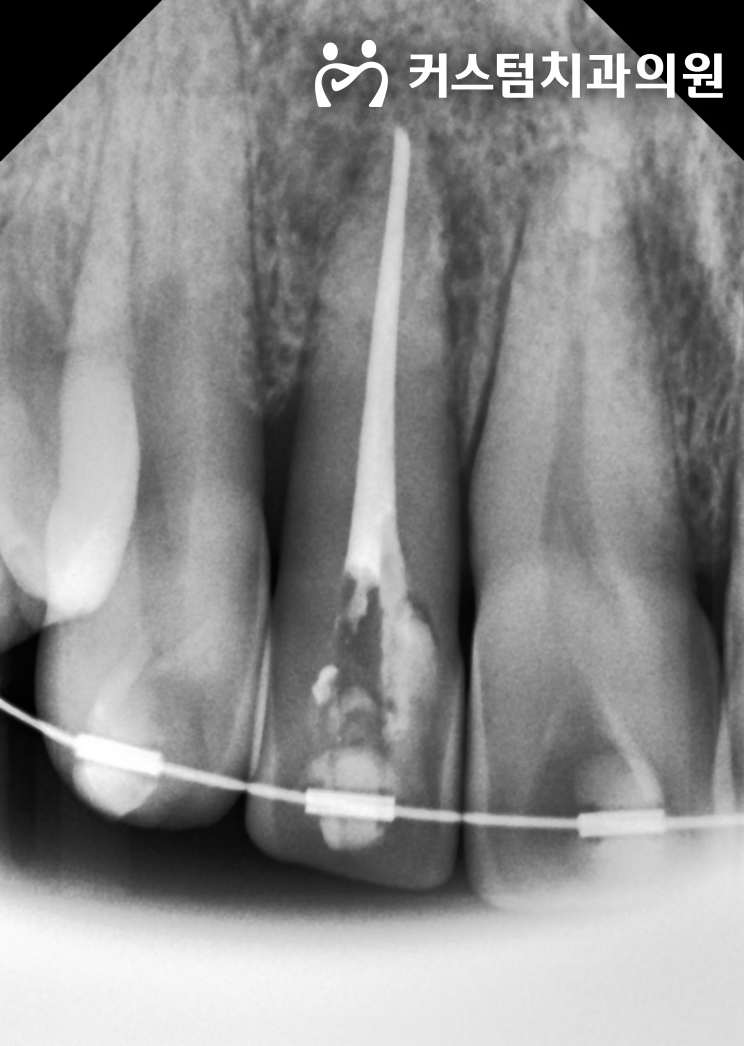

치열교정이 아닌, 병소의 원인을 제거하는 신경치료를 즉각적으로 시작했습니다.

위 사진은 2023년 10월 12일, 신경관 내부의 오염 물질을 제거하고 항균 약재를 첩포해 둔 치료 중간 과정입니다.

일반적인 신경치료에 비해 치료 기간이 수개월 단위로 길어진 이유는 염증의 크기 때문입니다. 뿌리 끝에 가득 찬 염증성 삼출물(고름)이 완전히 배농되고, 세균이 소멸하여 텅 빈 공간에 환자 본인의 잇몸뼈가 스스로 재생될 때까지 기다리는 물리적인 치유 기간이 반드시 필요했습니다.